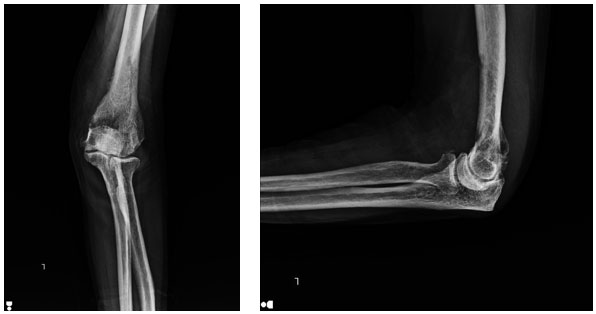

Ameliyat Öncesi: Röntgende humerus alt uçta düzensizlik görülmekte.

Akciğer Kanseri Kol Kemiği Metastazı | Distal Humerus Protez Uygulaması